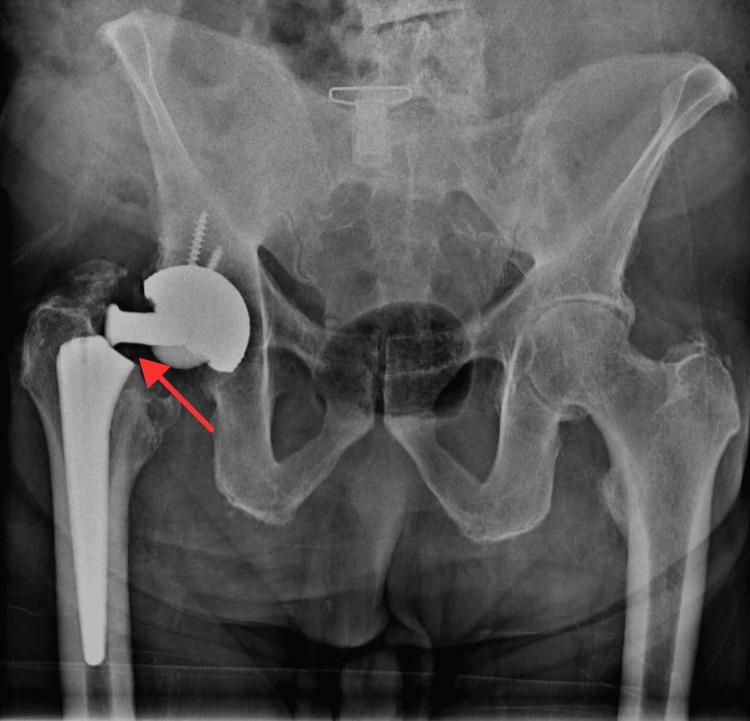

This case report presents a unique instance of a prosthetic neck fracture in an 81-year-old male with a CERAVER CERAFIT titanium (Ti6Al4V) femoral implant paired with a ceramic-on-ceramic total hip replacement. No fractures of the neck of a titanium femoral stem coated with hydroxy-apatite have been reported in the literature for this type of implant. The patient experienced a sudden, non-traumatic fracture, many years after his primary surgery. The report discusses the clinical presentation, diagnostic findings, known risk factors for femoral neck implant fractures, surgical management, and the outcome.

本病例报告呈现了一例独特的病例,一名81岁男性患者的人工股骨颈骨折,其使用的是CERAVER CERAFIT钛合金(Ti6Al4V)股骨植入物,并搭配陶瓷对陶瓷全髋关节置换。文献中尚未报道过此类涂层有羟基磷灰石的钛合金股骨干颈骨折。该患者在初次手术后多年发生了一次突发的、非创伤性骨折。报告讨论了临床表现、诊断结果、已知的股骨颈植入物骨折风险因素、手术治疗及预后情况。